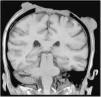

A 60-year-old woman receiving azathioprine for autoimmune hepatitis and Child-Pugh A liver cirrhosis consulted for an ulcer on the scalp that had first appeared 1 year previously. Physical examination revealed an irregularly shaped ulcer measuring 25 cm in diameter extending from the front hairline to the occipital region, with tumorlike lesions, necrotic hyperkeratotic areas, and infiltrating borders that bled to the touch (Fig. 1). The cranium was exposed, with destruction of parietal bone and exposure of the meninges. Biopsy confirmed a diagnosis of invasive squamous cell carcinoma. Computed tomography revealed the absence of enlarged lymph nodes and distant metastases. Magnetic resonance imaging of the brain revealed osteonecrosis and involvement of the pachymeninx but not the parenchyma (Fig. 2). Given the patient’s liver disease, treatment was started with cisplatin and concomitant external radiotherapy, during which the patient experienced a right hemisphere stroke. Follow-up magnetic resonance imaging revealed progression of the tumor and invasion of the brain. The patient died 6 months after diagnosis.